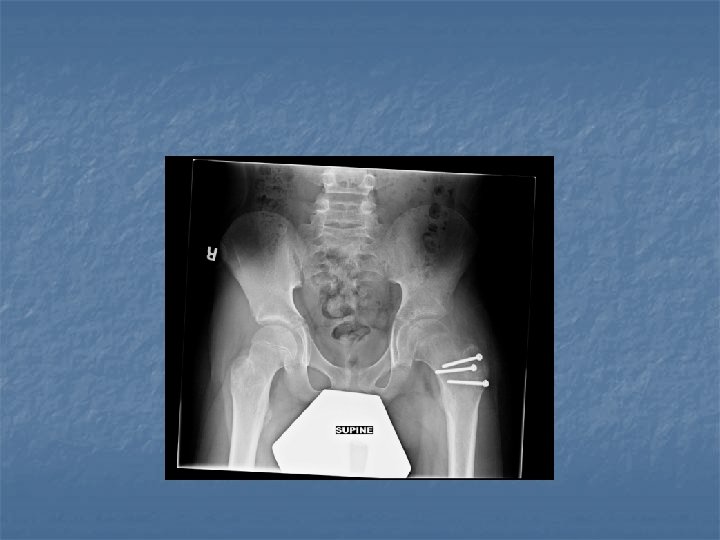

X-rays n n n Bones absorb x-rays and reflect image onto photographic film Used for bone injuries (breaks, dislocations) Provides clear images Can damage cells Cannot see soft tissue (muscle, organs)

Joint replacement n n When a natural joint is removed an artificial one is cemented in its place. Used for knees, hips, shoulders, fingers, and wrists